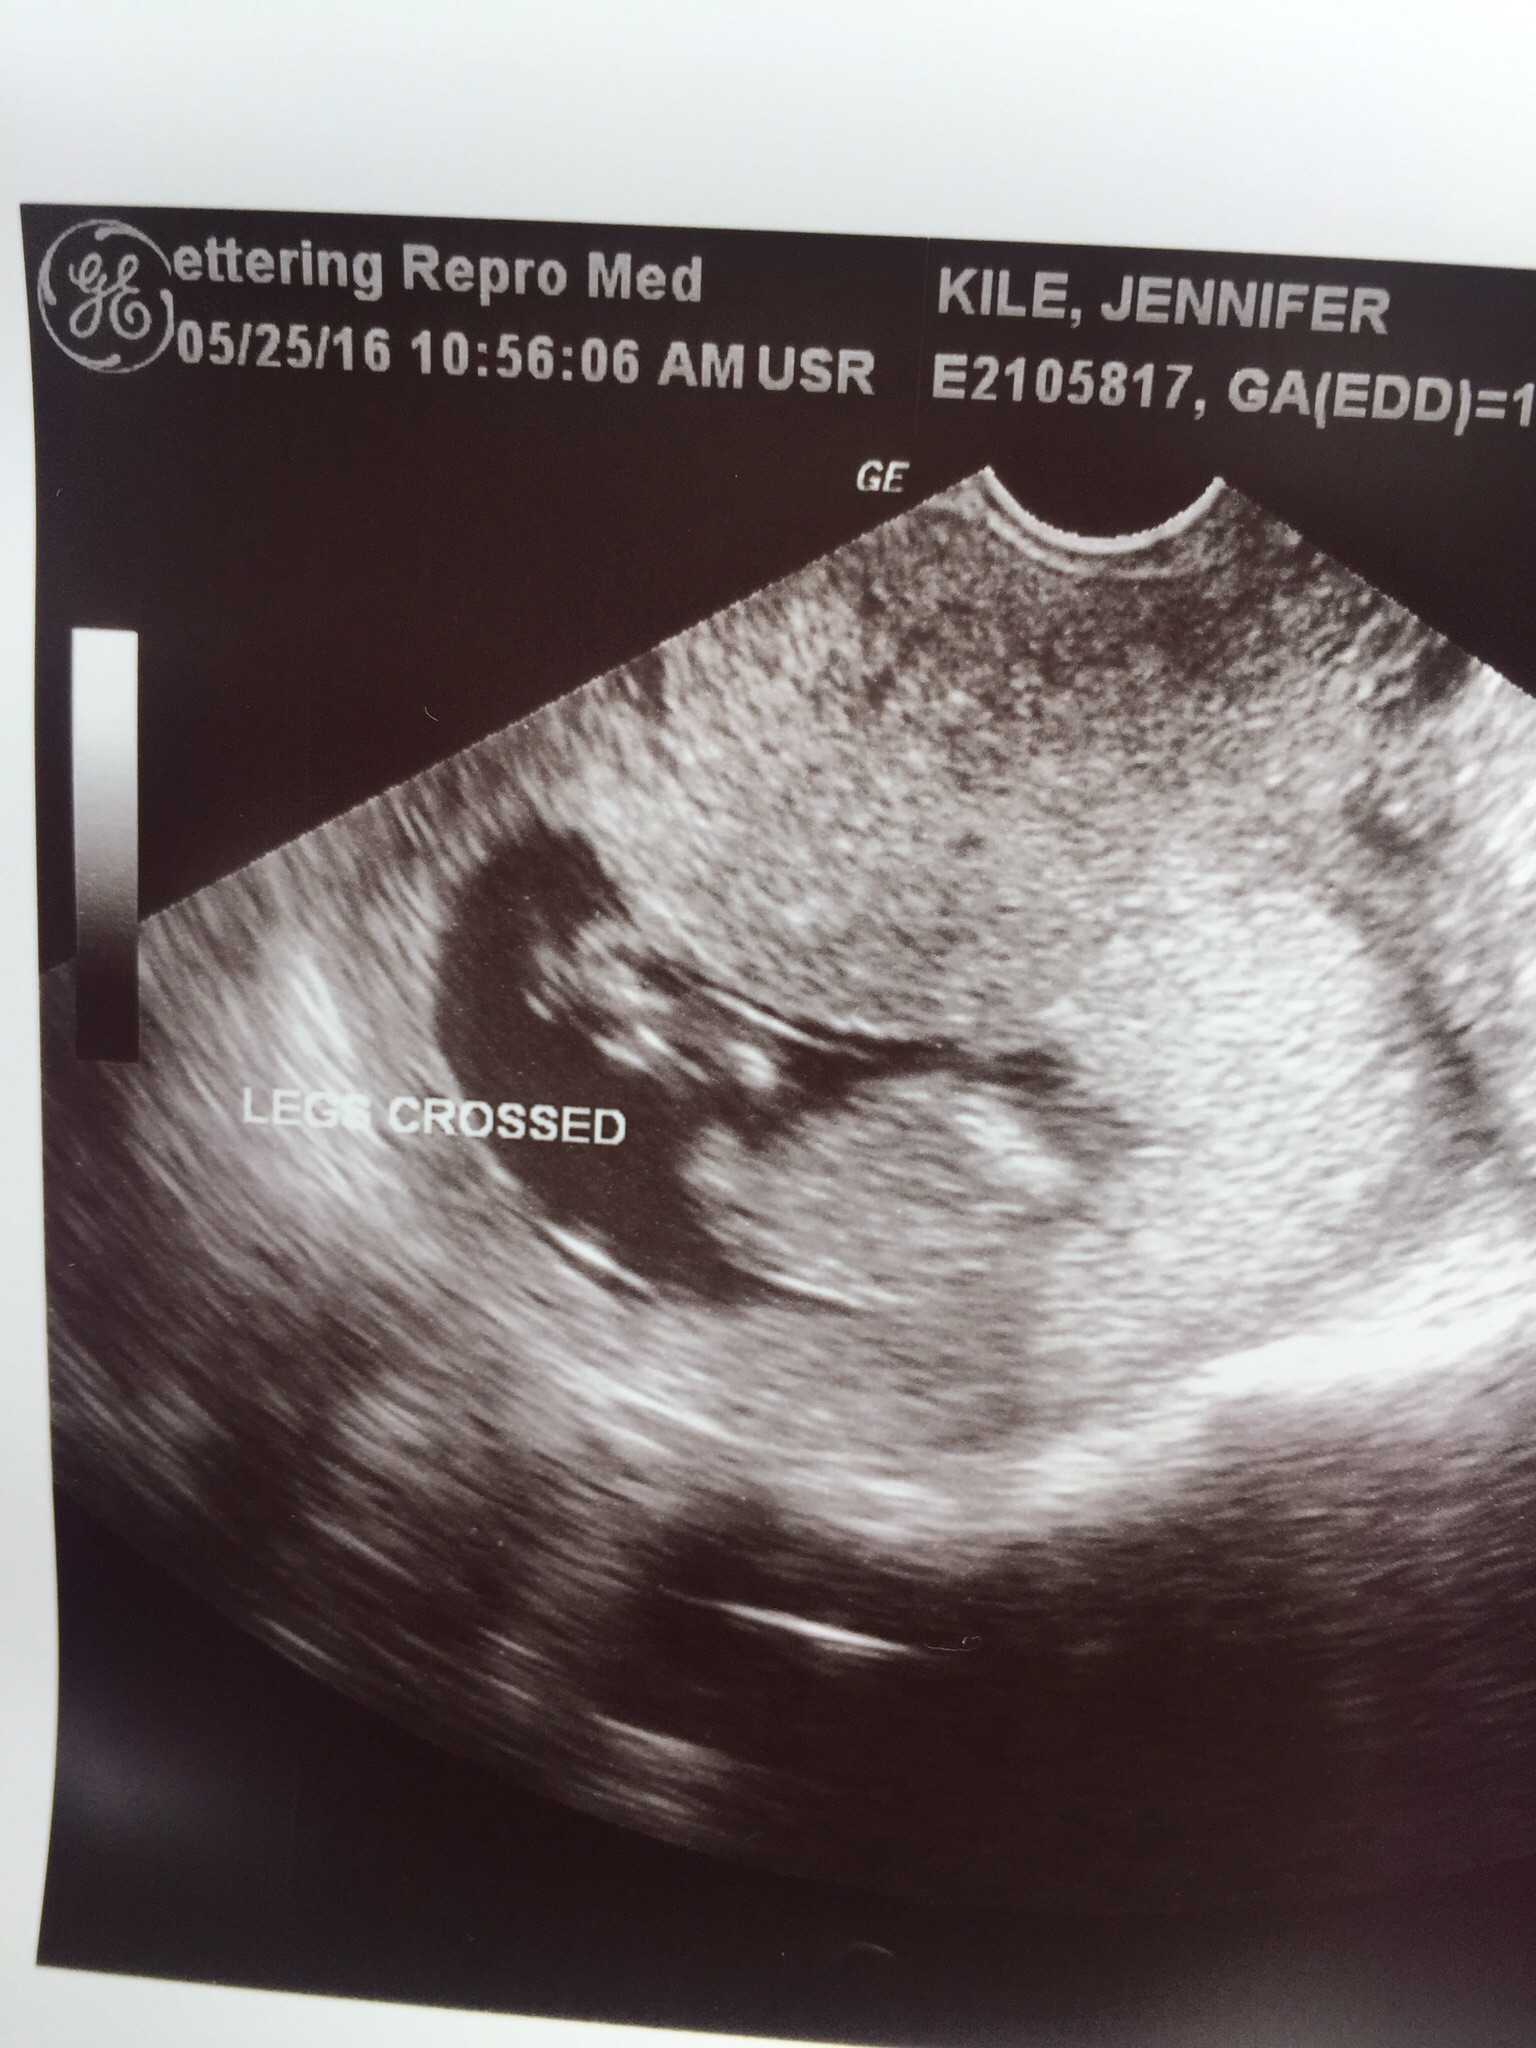

Thank you!!! Is it the angle that is making you guys think boy? Attachment 31462

I'm guessing I did the angle wrong? I swore since it's pretty flat (no nob) it looked like some girly ones I've seen. Just don't want to get my hubby's hopes up!

So my daughter's nub was at that angle at 13w with the the two lines, nub was just shorter. I honestly feel this is a pretty tricky nub.

I think 13w + gestation it would be more prominent if it is a boy. It could be a boy but I give higher odds for girl 70/30 %. I hope you get your boy.

The two things that I see are these. First pic, a pretty good angle on the nub, and the last pic looks like it may have a bump on the end which makes me think boy. Certainly not 100% on my guess by any stretch, could be a girl for sure but it's my beat guess.